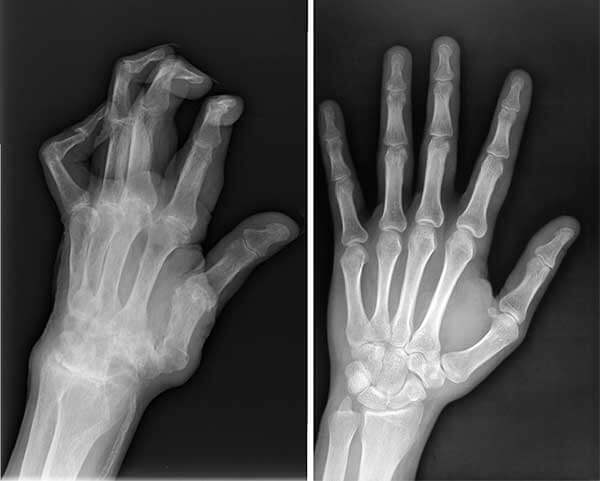

By the way, I am not the only one who was saved by this miracle product. My husband suffered from pain in his hands for a long time. His fingers were literally twisted, later he was diagnosed with arthritis. I decided to buy Maxiflex for him too. We drank the capsules together and Maxiflex helped him too.

X-ray of husband before and after taking Maxiflex.

My husband's hands before and after taking Maxiflex.